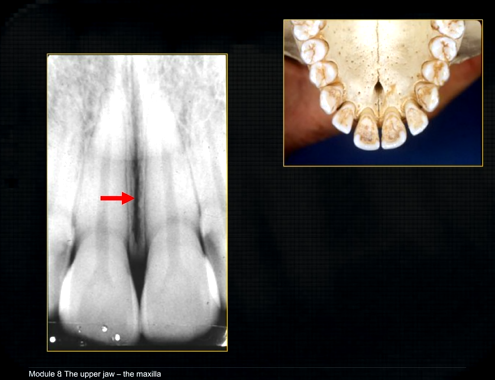

the upper jaw - the maxilla - what is circled in red?

the nasal cavity

what is seen here?

the nasal septum and the inferior nasal concha

what is the bottom arrow showing?

the floor of the nose - just above the apices of the upper anterior teeth

what can you say about the surface anatomy of the maxilla around the teeth themselves?

very undulating - prominences over roots

what is this thin line over the palate?

mid-palatal suture

what is this large hole?

naso-palatine foramen